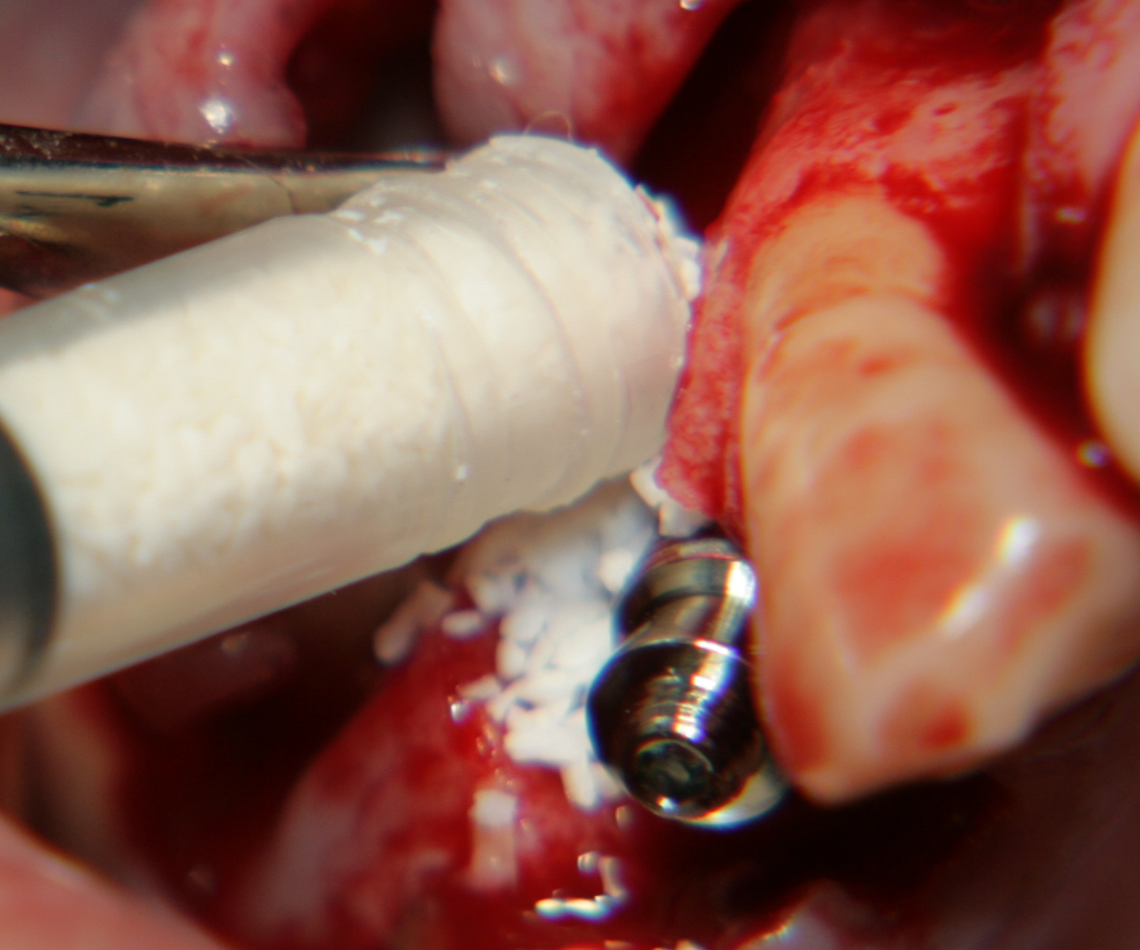

Около винтовете се поставя костозаместител, добре е да се размеси с

автогенна кост

Титанова мембрана

PRF